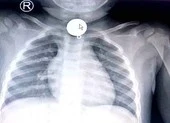

Sau khi thăm khám và chụp cắt lớp ổ bụng bệnh nhân, các bác sĩ (BS) phát hiện hình ảnh nghi dị vật (tăm) dài khoảng 5 cm xuyên thủng ruột vị trí hồi manh tràng, đâm vào cơ thắt lưng chậu phải gây áp xe và phản ứng viêm vùng hố chậu phải.